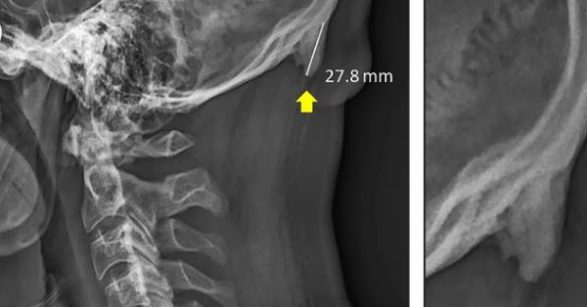

Hulumtuesit kanë gjetur në Universitetin e Australisë se të rinjtë kryesisht nga mosha 18-30 vjeç, janë duke e zhvilluar një rritje të çuditshme në anën e pasme të kafkës së tyre.

Studimi i bërë nga David Shahar dhe Mark Sayers kanë gjetur disa detaje shokuese. Pasi kanë mbledhur dhe analizuar të dhëna nga 1 mijë e 200 njerëz, nga mosha 18 deri 86, është gjetur se për disa arsye kjo rritje në kocka janë duke u rritur në adoleshentë dhe të rritur dhe numri i njerëzve me këtë problem është duke u rritur.

Çka e bënë edhe më interesante këtë gjë është kjo rritje prap kafkës së tyre duket si brirë. Disa media kanë raportuar se të rinjtë po rritin ‘brirë’ në anën e pasme të kafkës së tyre për shkak përdorimit të celularëve dhe teknologjisë së tepërt.